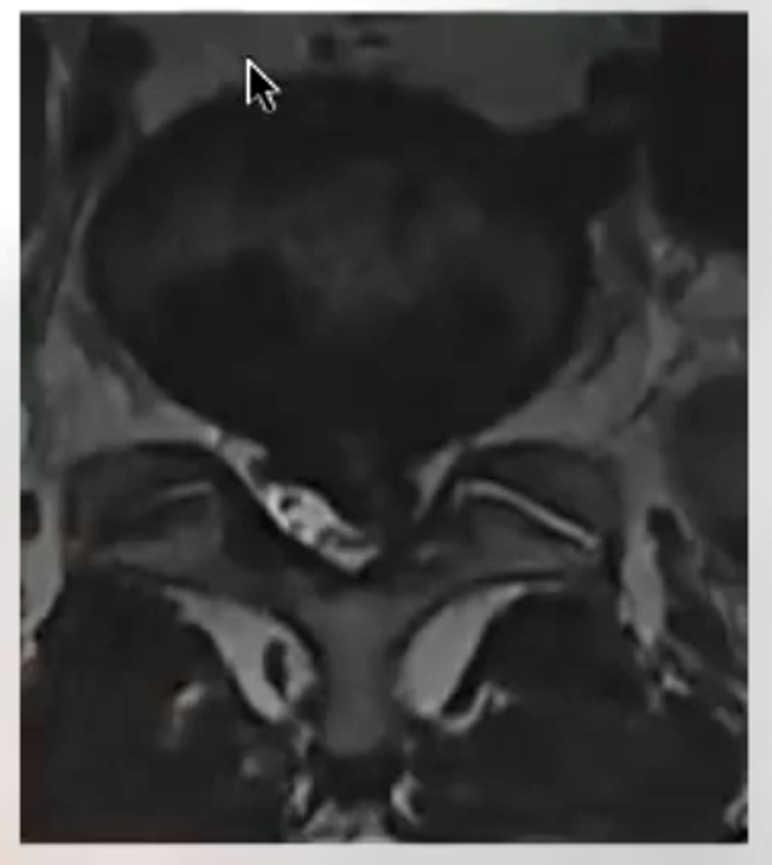

Our team treats patients who need repair of spinal deformities due to scoliosis, kyphosis, spondylolisthesis, infection, tumors, and trauma — following international standards of care.